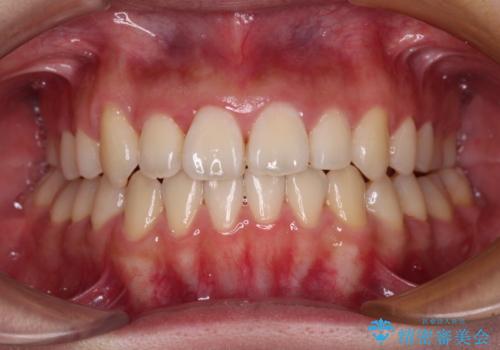

上顎骨を拡大することで、八重歯やデコボコを歯列に収めることができ、下顎の歯が外に位置していた奥歯の咬み合わせも改善することができました。

スペースも短期間に獲得できるため、1年程度で治療を終えることができました。